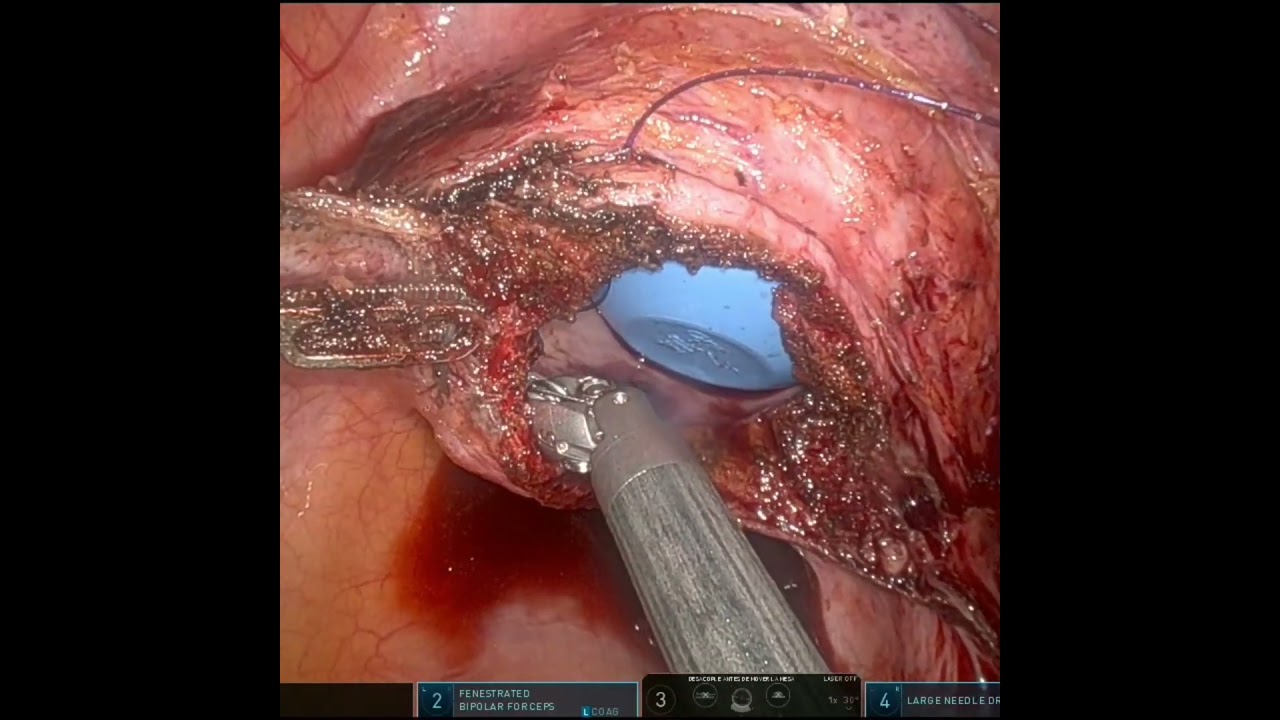

Cirugía Robótica Ginecológica